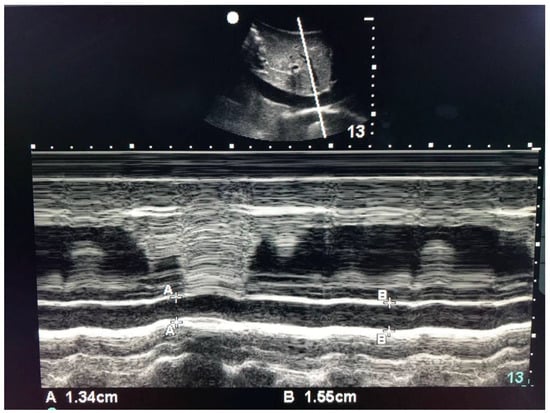

| IVC max diameter (cm ± SD) | 1.99 ± 0.31 | 2.05 ± 0.29 | 0.063 |

| IVC min diameter (cm ± SD) | 1.72 ± 0.33 | 1.74 ± 0.32 | 0.407 |

| CI index % | 14.0 ± 9.60 | 15.14 ± 11.18 | 0.416 |